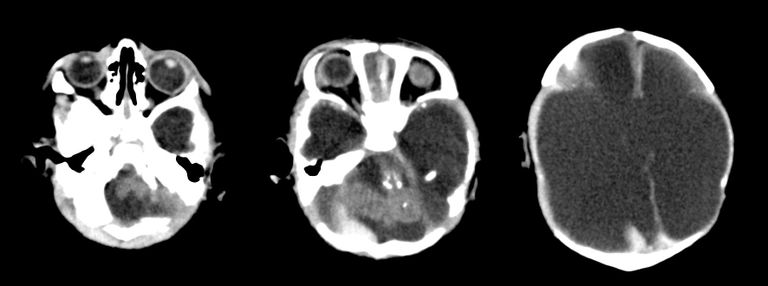

وقالت الصحيفة، إن دراسة صور الأشعة على المخ، وصور الموجات فوق الصوتية لـ 45 طفلًا برازيليًّا أصيبت أمهاتهم بالفيروس خلال فترة الحمل تبين أنه يمكن أن يلحق أضرارًا جسيمة بعدة أجزاء مختلفة من مخ الجنين أكثر من مجرد تشوه الرأس، وهي حالة صغر الرأس غير المعتادة التي أصبحت بمثابة العلامة الخبيثة لـ"زيكا".

وأوضحت أن الصور التي نشرت، أمس الثلاثاء، في دورية "علم الأشعة"، تشير أيضًا إلى احتمال خطير؛ لأن بعض الأضرار تحدث في مناطق الدماغ التي لا تزال في طور النمو بعد الولادة، وربما يواجه الأطفال الذين يولدون بدون تشوه واضح مشكلات عندما يكبرون.

من جانبها قالت الطبيبة ديبورا ليفين، وهي مؤلفة الدراسة وأستاذة الأشعة في كلية الطب بجامعة هارفارد، إن "المخ الذي ينبغي أن يكون هناك ليس هناك، والتشوهات التي نراها في الدماغ تشير إلى اختلال في عملية نمو المخ في وقت مبكر للغاية".

وتظهر صور الأشعة أن أهداف "زيكا" في المخ، التي يعرف بعضها الخبراء، تشمل "الجسم الثنفي" وهو الجزء الذي يسهل التواصل بين شطري الدماغ، والمخيخ الذي يلعب دورًا هامًّا في الحركة والتوازن والكلام؛ والعقد العصبية القاعدية التي تشارك في التفكير والعاطفة.